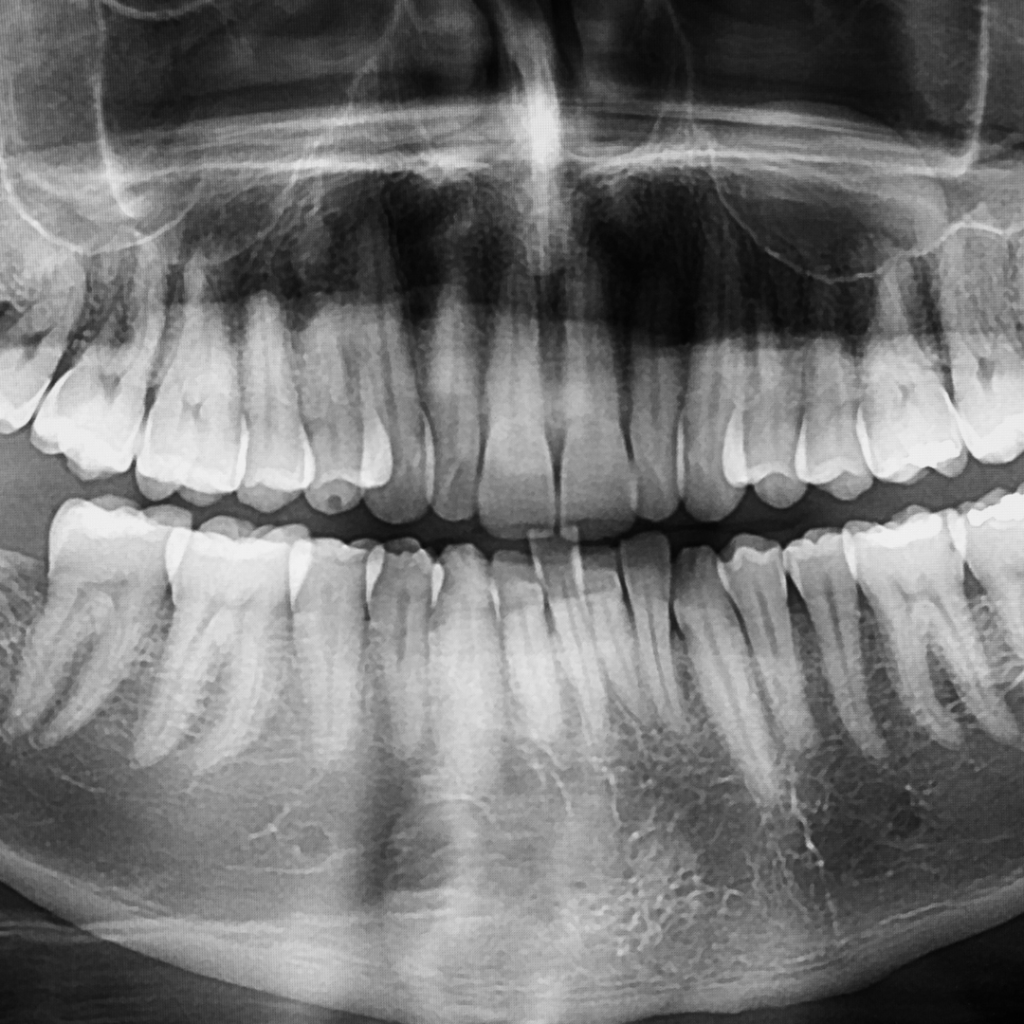

Your implant journey begins with a detailed consultation and assessment. This stage focuses on precision and personalization and typically includes:

- Complete oral and gum examination

- Digital X-rays or CBCT scans for accurate bone assessment

- Bite evaluation and smile analysis

- Discussion of a customized treatment plan based on your needs